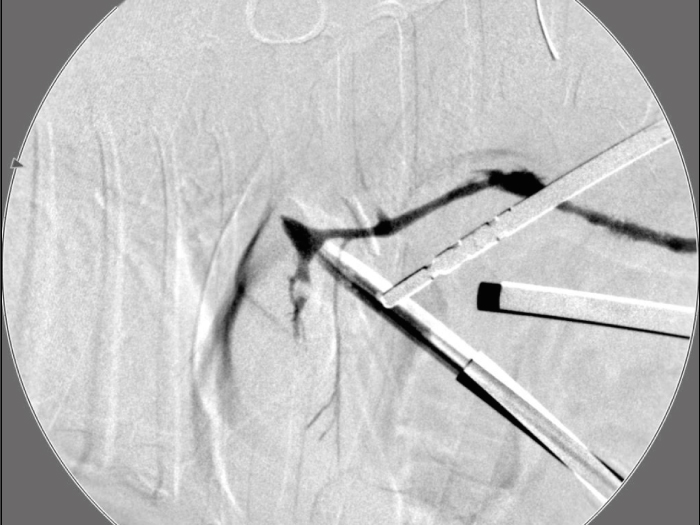

胆嚢の通路がちゃんと開通しているのか調べるために造影検査をしています。

この処置をすることで洗浄の効果と詰まりを確認することができます。

総胆洗浄をして詰まりがないかまずは確認します。(右)

きれいに開通していました。鉗子が大きく感じますが体が小さいので大きく見えます。

詰まりがないかを透視で確認しています。